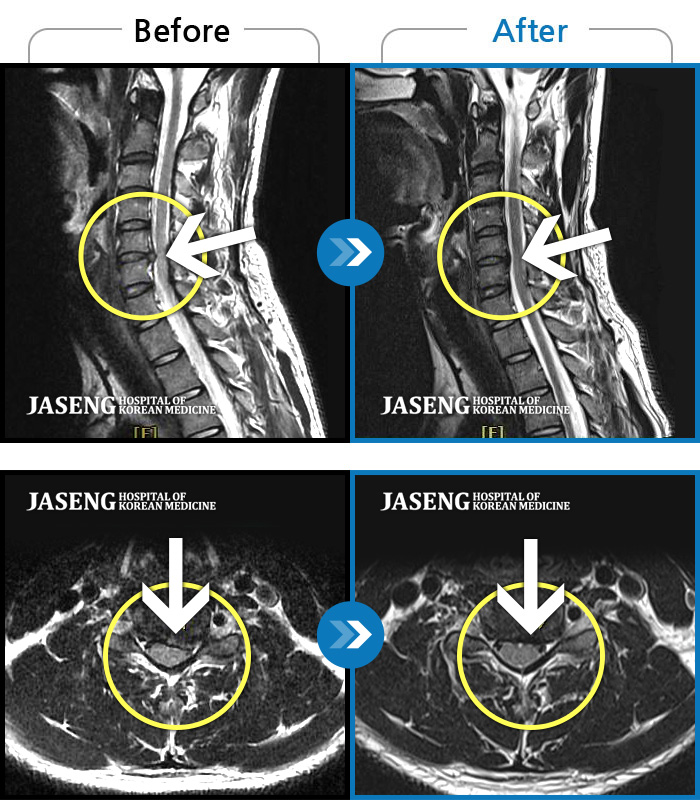

좌측 승모근부터 견갑골까지 이어지는 통증, 좌측 상완 비증으로 내원하셨습니다.

2024.04.03 ~ 2024.10.24